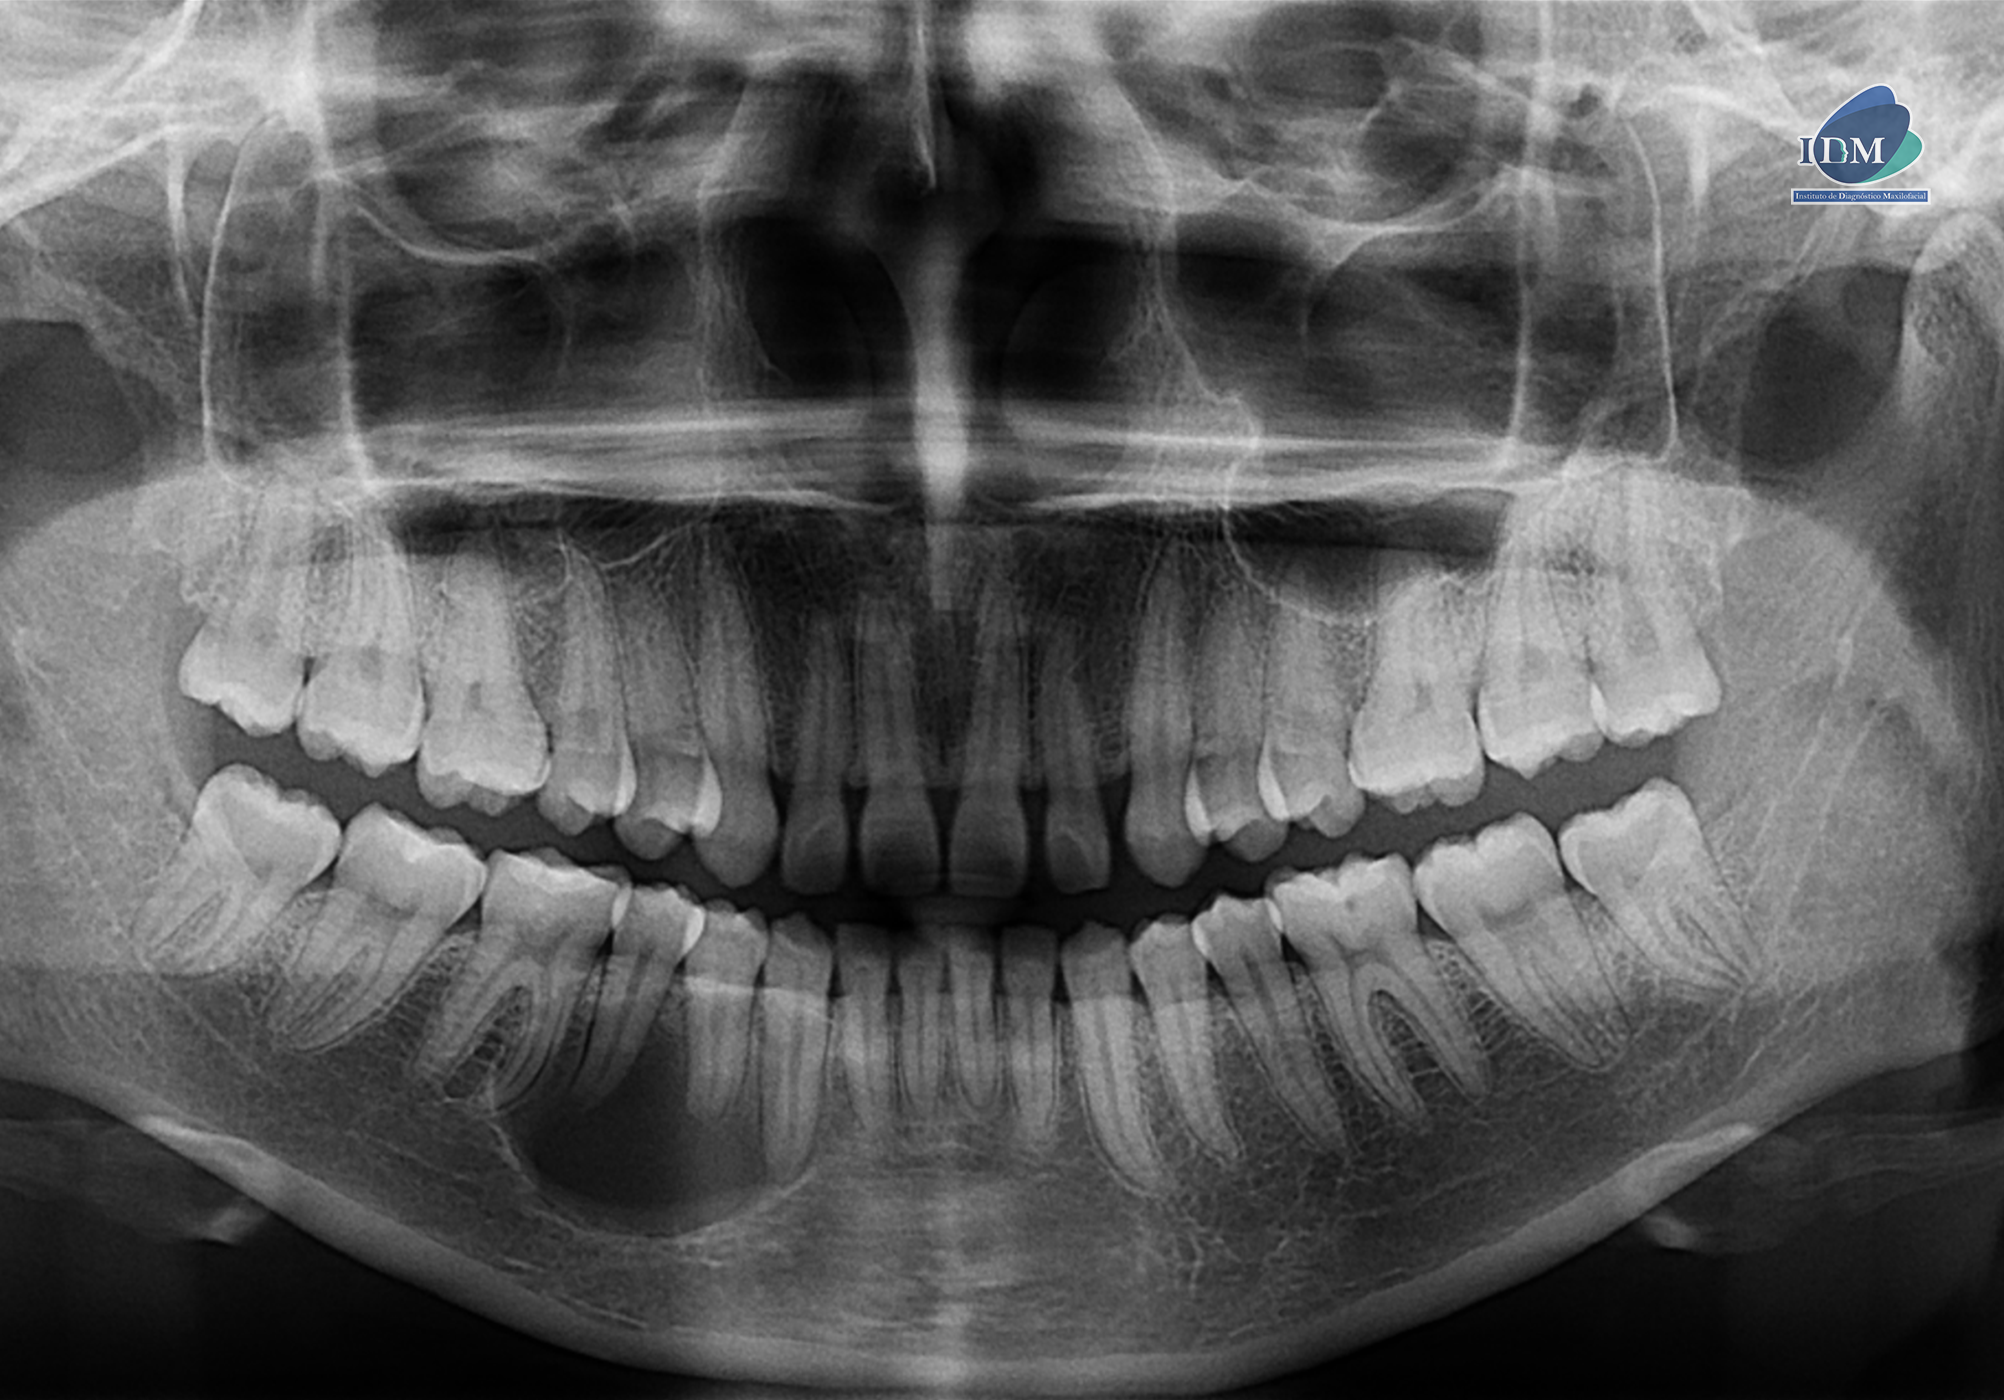

En la radiografía panorámica (Figura 1), se aprecia imagen radiolúcida unilocular, proyectada en cuerpo mandibular derecho, de limites definidos, bordes parcialmente corticalizados.

Radiografia Panorámica